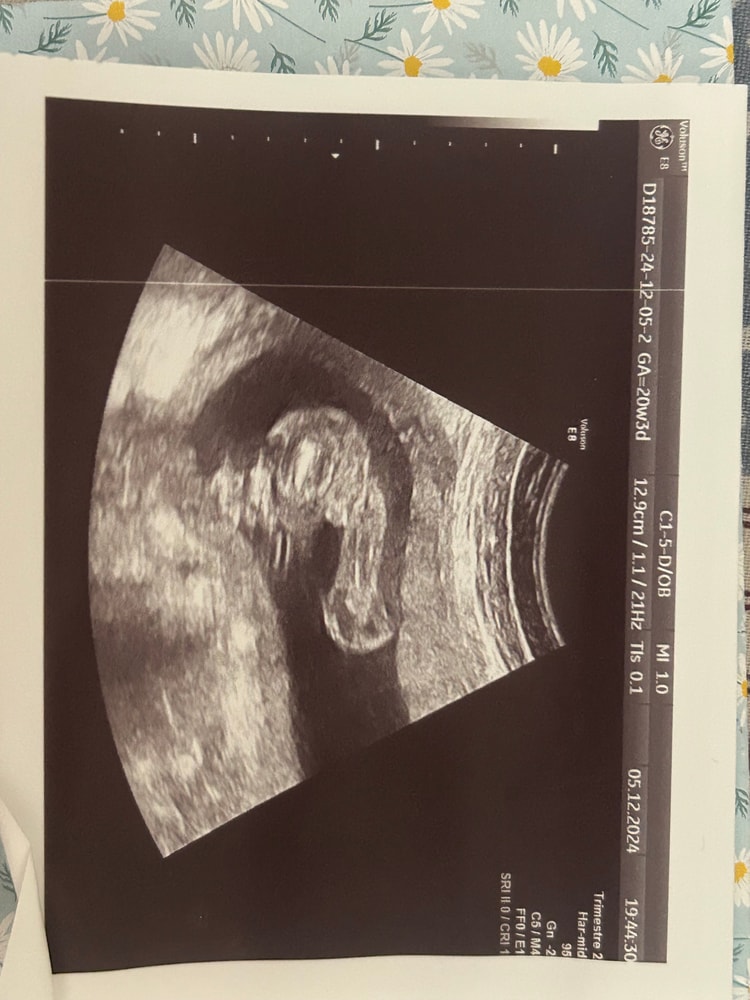

Arina в Клуб беременных 8 месяцев Пол малыша. Тут 20-21 нед🐣 Пол малыша Всем привет! Подскажите, пожалуйста 🙏🏻 это ведь мальчик? :) Посмотрите еще 20 записей на эту тему Лучший ответ Мама Лиля Пацан 23.03.2025 Ответить Отменить Ответить Лера Это мальчик 23.03.2025 Ответить Ольга На девочку похоже, если я правильно вижу))) 23.03.2025 Ответить Ольга Ольга , хотяяяяяя.... На последней фотке мальчик 23.03.2025 Ответить Сабрина я не разбираюсь, но интуитивно кажется что мальчик 🤔 23.03.2025 Ответить Лариса Тоже кажется, что мальчик. А врач кого предположил? 23.03.2025 Ответить Светлана По последней фотке- мальчик 23.03.2025 Ответить Пришел анализ на определение пола 😍 Пол ребенка Чаты Беременных Выберите чат: Январята-2026 Февралята-2026 Мартята-2026 Апрелята-2026 Майчата-2026 Июнята-2026 Июлята-2026 Августята-2026